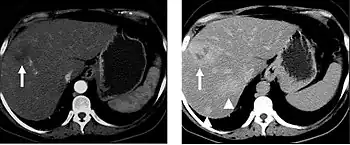

When evaluating hepatic masses, it can be advantageous to have both late arterial and portal venous phase images (biphasic imaging, figure 4) since some tumors enhance briskly during the arterial phase (hepatocellular carcinoma, hepatic adenoma, follicular nodular hyperplasia (FNH), and hypervascular metastasis), but may be occult or difficult to characterize on portal venous phase imaging alone (figure 6). However, it should be stressed that the addition of late arterial phase images is only indicated if one of these tumors is suspected, or if there is a need for further characterization of a hepatic mass, since the large majority of patients will not benefit from the addition of this phase. In addition, if there is a need to definitively characterize a hepatic mass, MRI is generally more sensitive and specific, with no associated radiation dose.

Transient hepatic attenuation differences in the arterial phase may mimic diseases of the liver.

FIGURE 7. Selected images from a renal mass specific protocol CT. Corticomedullary phase (axial 7a) demonstrates peripheral enhancement of the renal cortex with minimal opacification of the renal medulla. There is a large renal cell carcinoma in the left kidney (right in image) which can be differentiated from the normal renal parenchyma by the heterogeneous and differential enhancement. The renal artery and vein are opacified in this phase as well. The collecting system is not opacified (coronal reformat 7b). In the parenchymal phase, the renal cortex and the medulla are enhancing. The renal cell carcinoma in the left kidney is not as well defined when compared to the corticomedullary phase images, but is actually slightly more conspicuous. There is some contrast noted within the collecting system during this phase (7c).